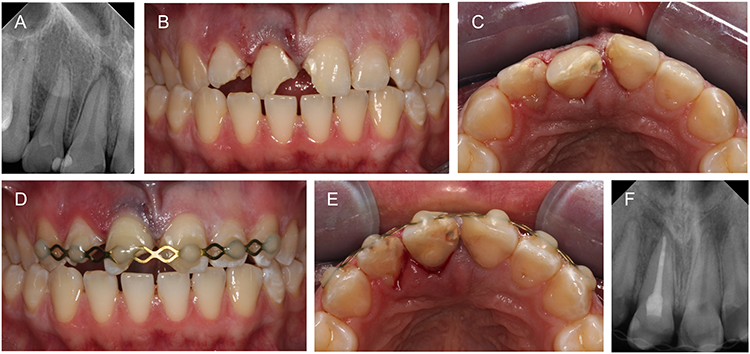

Intrudierte Zähne mit abgeschlossenem Wurzelwachstum sollten immer in die anatomisch korrekte Position bewegt, für 2 bis 4 Wochen geschient und bei schweren Intrusionen (> 2 mm) unmittelbar endodontisch behandelt werden, um externe entzündliche Resorptionen zu vermeiden. Bei Zähnen mit unvollständigem Wurzelwachstum ist eine Spontaneruption innerhalb weniger Wochen möglich, wenn die Intrusion weniger als 3 mm beträgt.

Die Spontaneruption ist mit den geringsten Heilungskomplikationen verbunden [17], und eine sofortige endodontische Behandlung wird wegen der Möglichkeit einer Revaskularisation, die in etwa einem Drittel der Fälle auftritt, nicht empfohlen [14,31,52]. Bleibt die Eruption aus oder ist die Intrusion größer als 3 mm, ist eine chirurgische oder kieferorthopädische Extrusion erforderlich. Bei einer Intrusion von mehr als 6 mm können diese Maßnahmen sofort eingeleitet werden (Abb. 4) [14,52].

Prof. Dr. Widbiller